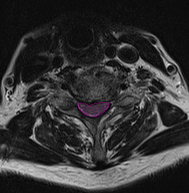

Στένωση αυχενικού σπονδυλικού σωλήνα με πίεση και παραμόρφωση του νωτιαίου μυελού. |